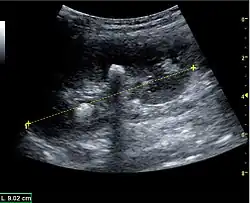

The length of the adult kidney is normally 10–12 cm, and the right kidney is often slightly longer than the left kidney. The adult kidney size is variable due to the correlation with body height and age; however, normograms for pediatric kidney size are available.[1]

Cortical thickness should be estimated from the base of the pyramid and is generally 7–10 mm. If the pyramids are difficult to differentiate, the parenchymal thickness can be measured instead and should be 15–20 mm (Figure 3). The echogenicity of the cortex decreases with age and is less echogenic than or equal to the liver and spleen at the same depth in individuals older than six months. In neonates and children up to six months of age, the cortex is more echogenic than the liver and spleen when compared at the same depth.[1]

Figure 3. Measures of the kidney. L = length. P = parenchymal thickness. C = cortical thickness.[1]

Figure 5. Simple renal cyst with posterior enhancement in an adult kidney. Measurement of kidney length on the US image is illustrated by '+' and a dashed line.[1] -